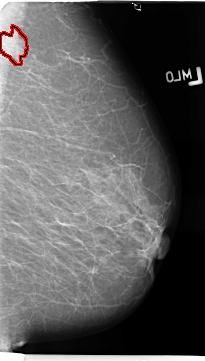

B_3137_1.LEFT_MLO

LEFT_MLO LINES 4688 PIXELS_PER_LINE 2656 BITS_PER_PIXEL 12 RESOLUTION 50 OVERLAY

FILE: B_3137_1.LEFT_MLO.OVERLAY

TOTAL_ABNORMALITIES 1

ABNORMALITY 1

LESION_TYPE MASS SHAPE IRREGULAR MARGINS SPICULATED

ASSESSMENT 4

SUBTLETY 4

PATHOLOGY MALIGNANT

TOTAL_OUTLINES 1